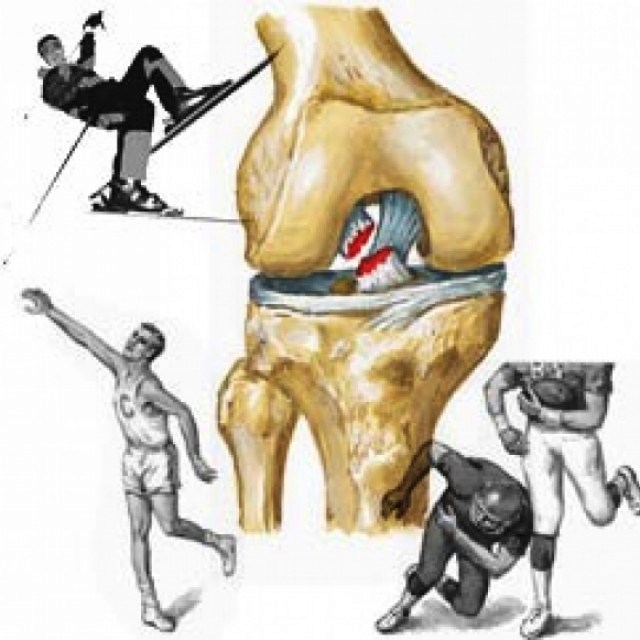

Причины и лечение травм коленного сустава